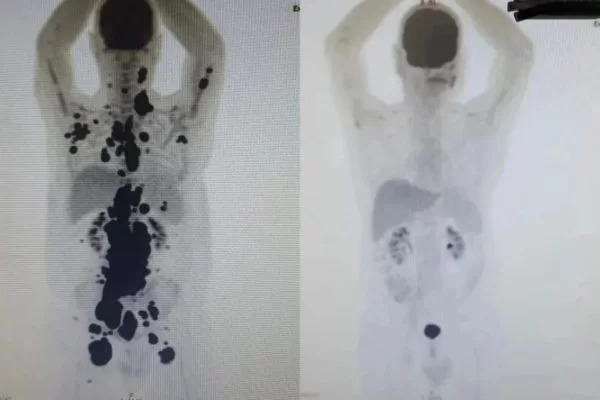

Um caso brasileiro emocionou muitas pessoas nos últimos dias. Isso porque um paciente, que lutava contra um tumor há 13 anos, apresentou remissão total do câncer após realizar um tratamento com a inovadora terapia Car-T. No último domingo (28), Paulo Peregrino, de 61 anos, recebeu alta do Hospital das Clínicas da Faculdade de Medicina da USP (HC-FMUSP), em São Paulo.

“O que foi extremamente animador é que vimos uma resposta positiva em apenas um mês em um paciente que já chegou muito debilitado no centro, com o câncer bem avançado, queixa de dor intensa e baixo índice de plaquetas, indicando que estava com a saúde bem afetada”, disse o médico hematologista Vanderson Rocha, que cuidou do caso, à Folha.

No caso do paciente brasileiro, o hematologista afirmou que agora, será preciso acompanhar o homem por cerca de cinco anos. Isso porque será preciso confirmar se houve a “cura” do câncer. “Mas em estudos desenvolvidos nos Estados Unidos, em torno de 50% dos pacientes de linfoma são curados com CAR-T.”